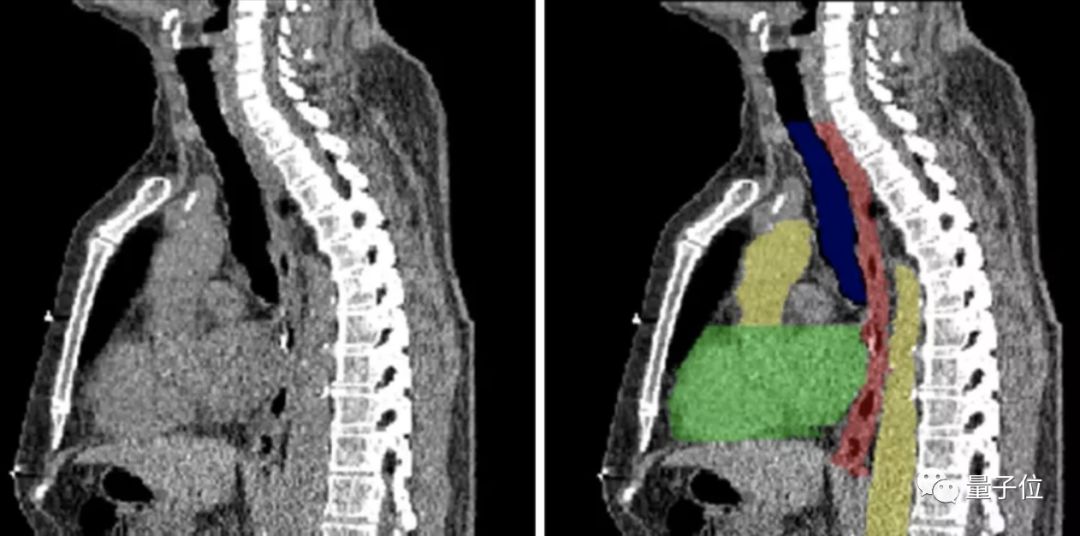

图像分割,顾名思义,就是将图像切分为多个区域,来简化或改变图像的表现形式,从而让图像变得更加容易解读和分析。

目前,图像分割技术用在了肿瘤和其他病理位置定位、组织体积测量、解剖学研究、计算机辅助手术、治疗方案制定以及临床辅助诊断等多个细分领域。

图像分割的实现方式也不难理解——以图像中的自然边界,例如物体轮廓、线条等,将图像切分为多个区域。

在计算机中,是对图像中的每个像素加上标签,并认为具有相同标签的像素有着某种共同视觉特性,从而来实现分割。

良好的图像分割模型,能有效帮助医疗机构提高医学影像判读效率,进而增强临床诊疗能力、提升疾病治愈率以及减少病患等待时间,弥补因医疗机构影像科资源缺乏带来的多种问题。

这就决定想要将图像分割应用到真正的医疗场景中,一方面需要基于不同的图像分割类型对模型进行优化,另外一方面则需要强大稳定的计算能力来完成推理。

怎么进一步落地?英特尔提供了工具,比如OpenVINOTM工具套件以及至强处理器系列产品等等, 能够在在保证 U-net 模型高准确率的同时,推理时间大幅降低85%。

在报告中不仅给出了具体的使用方法,也放出了不少已经落地的案例,比如东软的eStroke溶栓取栓影像平台,西门子的心腔检测和量化模型等等。